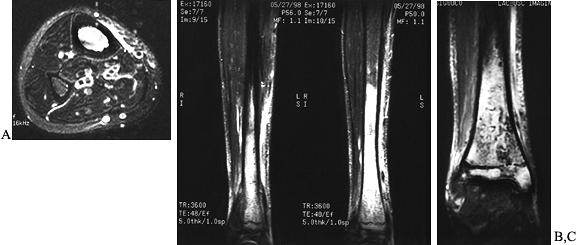

information. Do sinograms whenever there is a sinus tract or open

draining area from which the depth and extent of the infection can be

determined (Fig. 133.4).

Do abscessograms whenever an abscess is present and frank pus is

aspirated. The abscessogram will help outline the extent of the abscess

cavity (Fig. 133.5). MRI, computed tomographic scanning, and radiographic tomogram are all useful tools in evaluating osteomyelitis.

Figure 133.4. Anterior (A) and posterior (B) roentgenograms of a sinogram in a 21-year-old man with chronic osteomyelitis that tracks into the intramedullary cavity.

Figure 133.5. Lateral radiograph (A) of a 15-year-old boy shows a subperiosteal abscess that was aspirated and injected with contrast material. Anteroposterior (B) and lateral (C)

radiographs of a 9-year-old child show contrast material in the subperiosteal area and within the medullary cavity after pus had been aspirated. The contrast material demonstrates the extent of the abscess. |